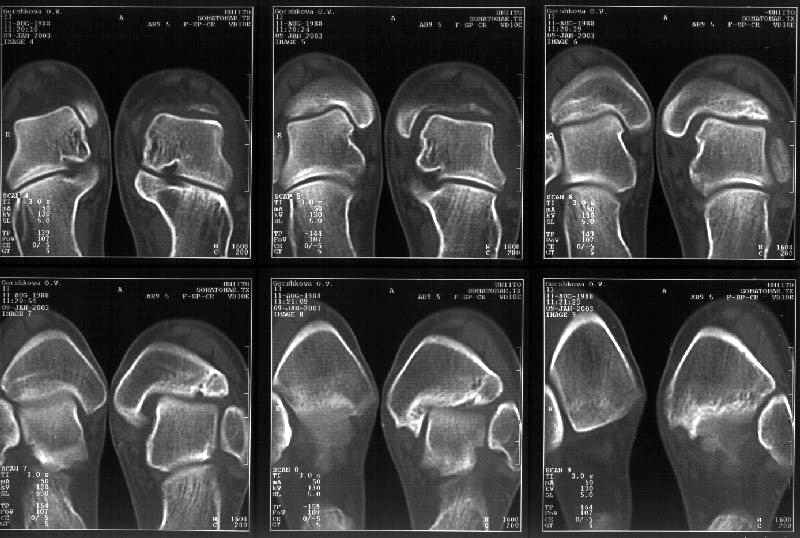

На следующий день пациентке сделали КТ. Может быть, после просмотра картинки будут другие предложения? Не убрать ли ве-таки этот фрагмент

позади внутренней лодыжки, который оттесняет таран кнаружи?

Думаю, КТ прочитан не верно. Задняя часть медиального маллеола, в сущности уже часть заднего маллеола стоит на месте и трогать её не следует. Передняя часть маллеола на 3-4 мм удалена от тарана. Сравните с пространством между

латеральным маллеолом и тараном. В норме все три должны быть одинаковы: между тараном и латеральным, задним и медиальным. Это главное условие устойчивого сидения тарана в голеностопном суставе.

Все-таки она как раз была была отколота и вместе с тараном смещена латерально.

Внутренняя лодыжка не была сломана, она как была на своем месте, так там и находится. Это таран от нее отдавлен кнаружи смщенным в его сторону фрагментом позади внутренней лодыжки. За счет чего и есть проявления нестабильности связок.

Вот и проблема. Восстанавливать ли эту равномерность сейчас, и если да, то как. Вот точка зрения коллеги из Штатов:

Мне в тоже время совершенно ясно видно по той же КТ, по 4 срезам, расположенным в центре и вверху пленки, что перелома внутренней лодыжки не было, в следующем собщении я приложу увеличенный фрагмент томограммы. А к этому письму прилагаю увеличеный фрагмент послеоперационной рентгенограммы, где выделил отколотый фрагмент

позади внутренней лодыжки. И он, как я вижу, находится между стержнем и тараном. А перелома внутренней лодыжки, и тем более смещения, IMHO

не определяется.

Здесь 4 среза, начиная от основания лодыжки и проксимальнее. Где, по Вашему мнению, проходит линия перелома, отделяющая переднюю часть внутренней лодыжки от большеберцовой кости? Заранее спасибо.